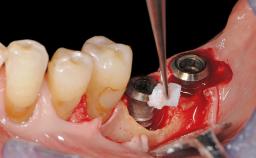

Late Presentation of Peri-Implant Mucositis Requiring Soft-Tissue Augmentation and Esthetic Crown Lengthening at Implant Site 11